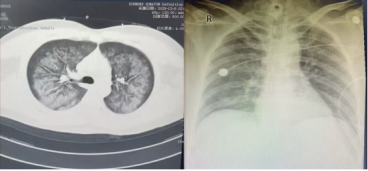

左图12月8日胸部CT,右图12月14日床旁胸片

当天14时前,遵医附院重症医学团队抵达该院ICU,即刻投入抢救。该30岁男性患者因“咳嗽、咳痰1月余,呼吸急促伴咯血12+小时”入院。1月前受凉后咳嗽咳痰,自服感冒药无效;12+小时前突发剧烈咳嗽、气促、鲜红色咯血及呕吐咖啡色胃内容物,家属于当日凌晨3时25分送至松桃县人民医院急诊科,经胸部CT诊断为“肺部感染”,收入重症医学科。

当日20时,团队护送患者带机转运至遵医附院重症医学科。入科查体,T37.2℃,R20次/分,P123次/分,BP113/66mmHg(大剂量升压药维持),SPO₂96%;患者气管切开接转运呼吸机通气,呼之能应,双肺呼吸音粗、可闻湿性啰音。科室ECMO治疗护理小组立即接管患者,制定个性化综合诊疗方案。治疗期间密切监测血流动力学参数,动态追踪炎症指标及肝肾功能、凝血功能等,通过心脏彩超精准评估容量,予VV-ECMO、镇静镇痛联合呼吸支持,同步开展抗感染、抗休克、血液透析(兼顾容量管理与炎症清除)、脏器保护、营养支持等治疗。

经精准救治,患者病情逐步好转,肺部感染得到控制,于12月13日顺利撤机,后续继续气管切开呼吸机辅助通气。随着炎症指标下降,呼吸机参数逐步下调,患者自主呼吸恢复良好,12月17日拔除气切套管并封堵切口,配合康复团队完成阶梯式康复训练,12月19日顺利转回松桃县人民医院继续治疗。